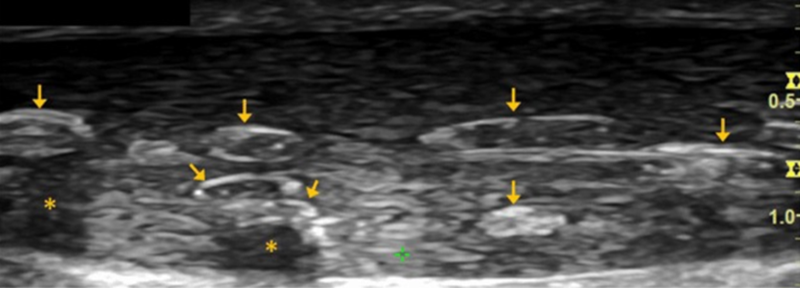

跟腱焦磷酸钙沉积病

箭头显示在椎间后关节周围和左侧C6/7神经孔内的炎症过程增强